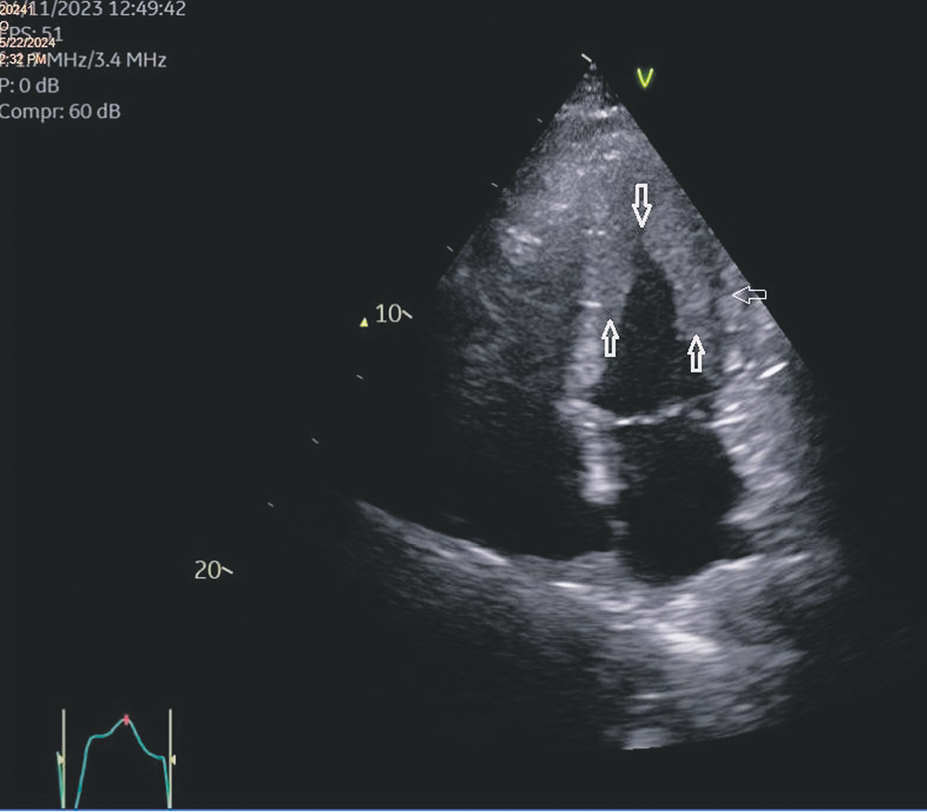

EchoCG showed hypercontractility of the basal and mid-LV segments associated with local akinesia of the apex (Merlon’s sign) and significant wall masses, which were initially believed to be extensive thrombotic deposits. These masses were localized in the area of the fixed apex and in the protrusion of myocardium with preserved contractility (Fig. 5). A similar condition was observed in the region of the outflow tract and the apex of the right ventricle (Fig. 6). LV systolic function was preserved. No echocardiographic evidence of severe diastolic dysfunction was noted.

Fig. 6. Echocardiographic changes in the right ventricular outflow tract: a — short-axis view at the level of the aortic valve, subcostal approach, reveals parietal masses located in the outflow tract of the right ventricle, indicated by the lower arrow. The arrows above and to the right delineate the myocardium of the right ventricle and a clear boundary between the myocardium and the parietal deposits. For comparison; panel b — displays the same section from a healthy individual,demonstrating a non-thickened right ventricular myocardium absent of pathological parietal masses